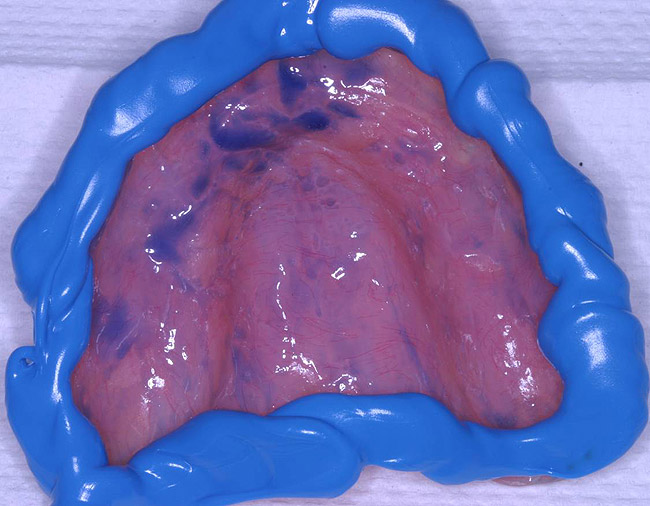

The patient's tissues were freed of excess saliva while the impression material (Take 1 Fast Set Tray Material, Kerr Corporation) was placed on the denture borders chairside (Figure 6). The denture was placed to begin the modified functional impression process and the standard border-molding adjustments to capture the details of the mu cco-buccal folds. After the 4-minute set time recommended by the manufacturer, the denture was removed and the impression was checked for insufficiencies (Figure 7). Once the border mold was deemed acceptable, a low-viscosity impression material (Take 1® Fast Set Wash Material, Kerr Corporation) was extruded onto the palatal area of the denture/tray to finely capture the necessary details of the edentulous mucosa (Figure 8 and Figure 9). A fluid, low-viscosity material is optimal for achieving this result and minimizing unwanted pressure on the maxilla. Again,the standard border-molding techniques were observed to ensure proper integration with the high-viscosity impression material and properly control the impression accuracy. The recommended 4-minute intraoral set-time was observed.

Figure 8  Take 1 Impression material to be used as a wash for the remainder of tissue detail.

Figure 8

Figure 9  Final detailed impression to be immediately poured up.

Figure 9

Figure 10  Final upper impression poured up in stone.

Figure 10